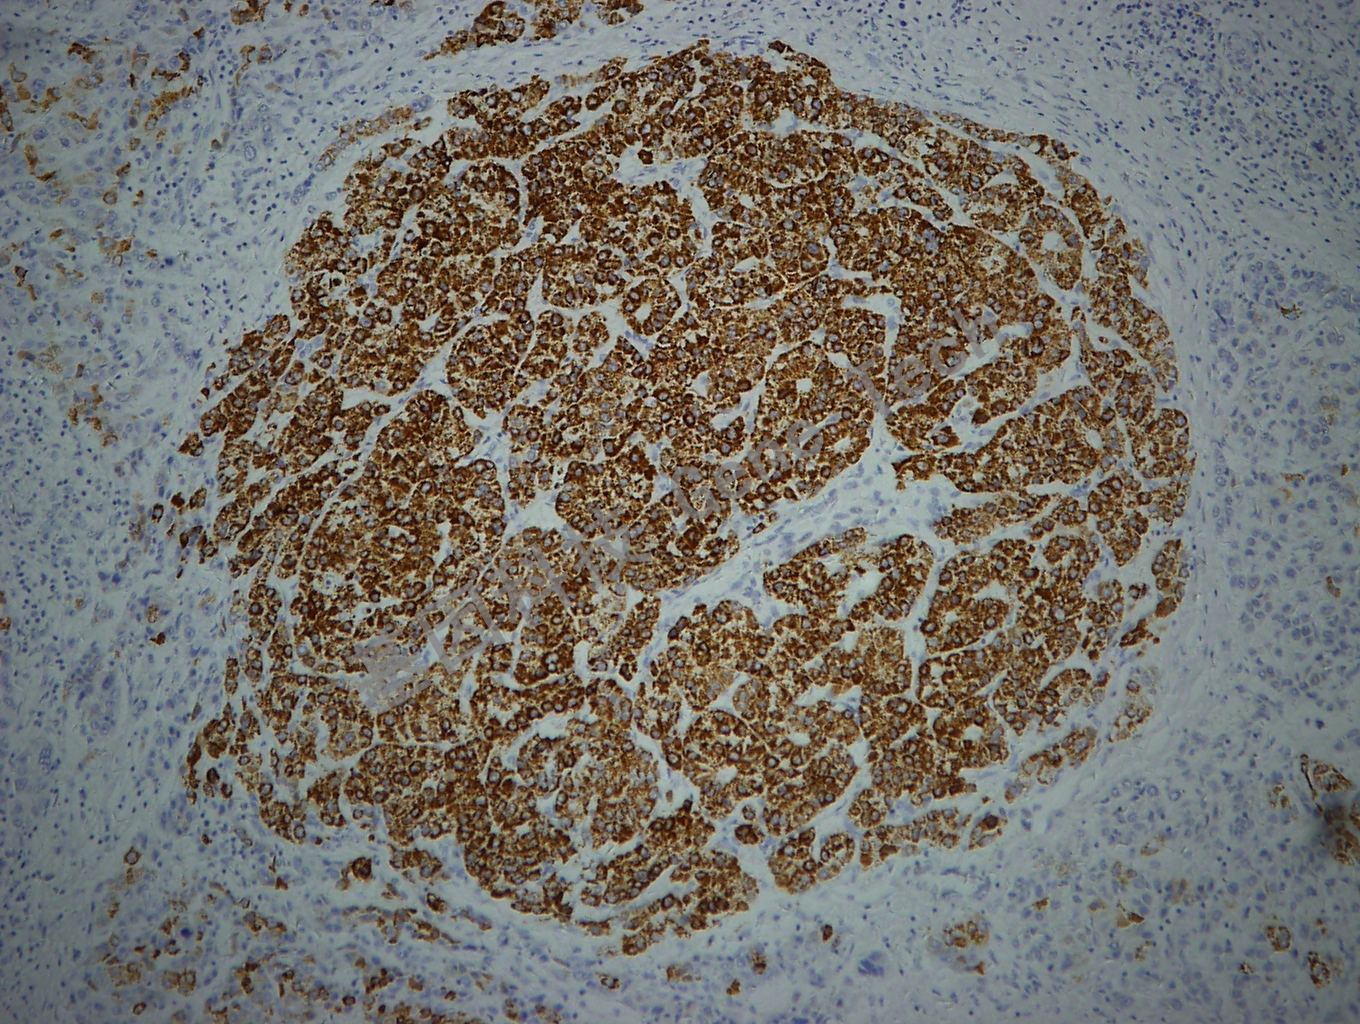

| 克隆號(hào):OCH1E5 | 種屬:鼠 | 適用染色系統(tǒng):GTvisionTM |

| 預(yù)處理:高pH熱修復(fù) | 陽(yáng)性部位:細(xì)胞漿 | 陽(yáng)性對(duì)照:肝癌 |

| 簡(jiǎn)介:Hepatocyte又稱Hep Par-1,是肝細(xì)胞的特異性標(biāo)記物,識(shí)別肝細(xì)胞的線粒體。在肝臟中顯示彌漫性的細(xì)胞質(zhì)染色,伴有特性的顆粒狀染色??陕?lián)合Arginase-1和Glypican-3用于原發(fā)性肝細(xì)胞癌與轉(zhuǎn)移性腫瘤及膽管癌的鑒別診斷。 | ||

| 肝癌石蠟怕,用 Hep Par-1(GM7158)染色,細(xì)胞漿陽(yáng)性,DAB 顯色。 | ||